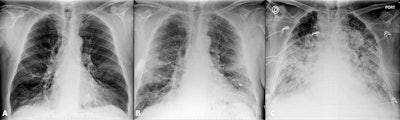

Italy

Italy was quite hard hit, said Dr. Nicola Sverzellati, head of the radiology unit at the University Hospital of Parma. The country's first patient, a 38-year-old man, presented at an emergency department in Codogno in February with acute respiratory distress syndrome. Only a few weeks later, the government locked Codogno and neighboring villages down. As the virus spread through the country, clinicians across Italy began tracking chest CT features of COVID-19, including ground-glass opacities, multilobe involvement, bilateral distribution, and posterior involvement.